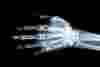

If you have any doubts about how serious your injury is, go to A&E so your wrist can be checked by a medical professional. An X-ray is the most reliable way to tell if your wrist is broken or badly sprained, so doctors can recommend the most appropriate form of treatment.